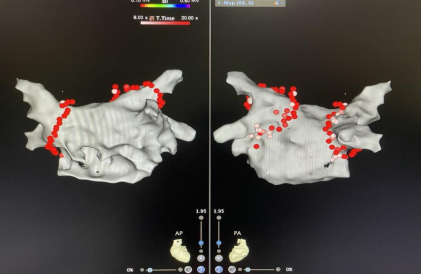

環(huán)肺靜脈隔離術(shù)